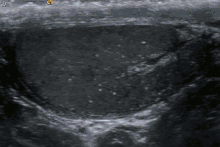

The cause is unknown, but this condition has been associated with testicular cancer in a small group of individuals, cryptorchidism, mumps, infertility and intraepithelial germ cell neoplasia. Classic testicular microlithiasis is defined as five or more echogenic foci per view in either or both testes, and limited testicular microlithiasis defined as one or more echogenic foci that do not satisfy the criteria for classic testicular microlithiasis. In 80% of cases, both testicles are affected.

Testicular ultrasound